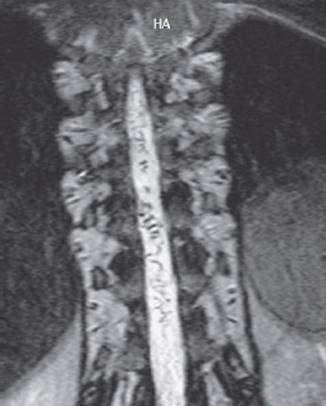

Fig. 4.4 Three-dimensional reconstruction of the cervical spine by spiral CT (gyroscan; courtesy of PD Dr. H. Spiess, Neuroradiological Institute, Talstrasse, Zurich, Switzerland).

MR angiography. When the spin-echo technique is used in MRI scanning, flowing blood gives rise to a signal only if it is excited by two radio wave pulses arriving one after the other at the same location. If the blood rapidly passes through the imaging plane, the bit of blood that received the first excitatory pulse has already flowed away by the time the second pulse arrives and no signal is generated—the vessel appears dark (there is a “flow void”). However, if the blood flows slowly enough to receive both pulses in the imaging plane, the vessel appears bright. When gradient-echo sequences are used, flowing blood always appears bright, while stationary tissue appears dark. Computer algorithms can combine the individual sectional images, processing them to generate a projectional image resembling a conventional angiogram; this is a magnetic resonance angiogram (Fig. 4.7). With MR angiography, an occluded carotid artery, for example, can be diagnosed noninvasively. Contrast-enhanced MR angiography is currently being performed increasingly often. In this technique, the signal is produced not by the flowing of the blood per se, but by the contrast medium in the bloodstream.